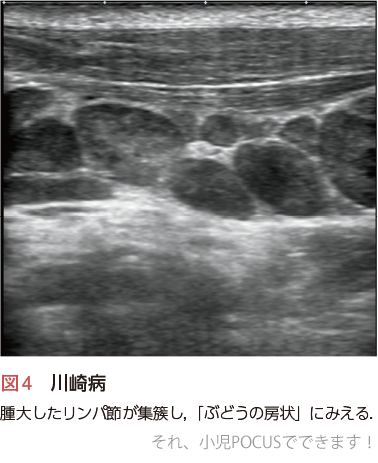

3)川崎病

ウイルス感染に関連するリンパ節腫大と類似した所見を呈しますが,腫大したリンパ節が複数集簇し「ぶどうの房」のように見えるといわれます3)〔また,診断基準4)に「非化膿性頸部リンパ節腫脹」とあるように,膿瘍化しないことが特徴です(図4)〕.